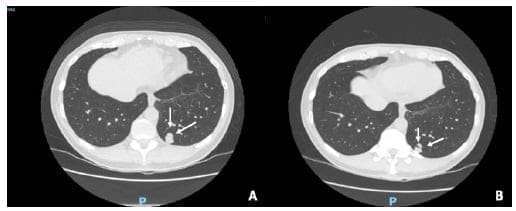

El paciente de la biopsia no conclusiva, que no aceptó una segunda intervención para confirmación histológica, ha tenido aproximadamente dos años de seguimiento radiológico y no ha presentado cambios en la morfología y tamaño del nódulo pulmonar (Figura 1).

Figura. 1. Paciente en seguimiento de nódulo pulmonar. A. Tomografía axial computarizada del año 2018, donde se identificó un nódulo (flechas), al cual se realizó biopsia percutánea, con reporte de patología negativo para malignidad. B. Hallazgos imagenológicos del mismo nódulo pulmonar a los 2 años de seguimiento, sin cambios respecto a estudio previo.